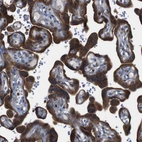

Immunohistochemical staining of human lymph node shows moderate to strong cytoplasmic positivity in non-germinal center cells.